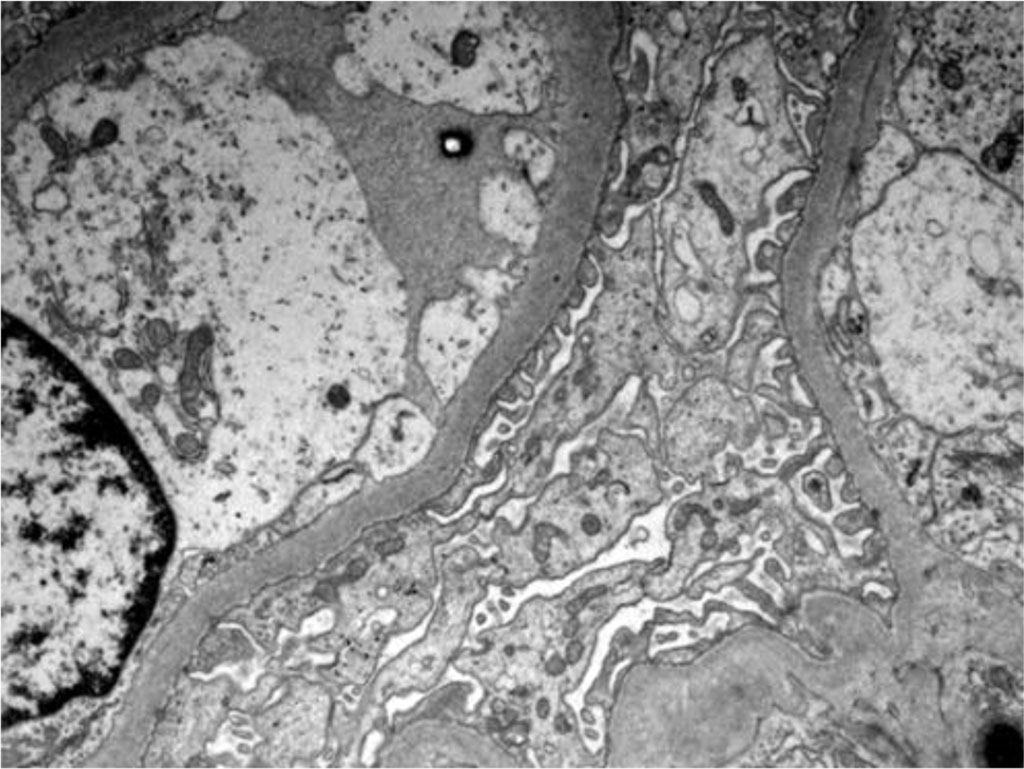

Figure 4. Electron microscopy - Podocytes foot process effacement

Figure 5. Electron microscopy - Podocytes foot process Effacement

An important way to confirm hantavirus infection is by renal biopsy. The histological findings in hantavirus nephritis are peritubular capilaritis without important tubulitis and hemorrhage is limited in the medulla [5]. Interstitial oedema and inflammatory cell infiltrates (lymphocytes, monocytes, macrophages and polymorphonuclear leucocytes) are usually seen. In electron microscopy, podocytes foot process effacement was described in some studies with hantavirus infection [9,10]